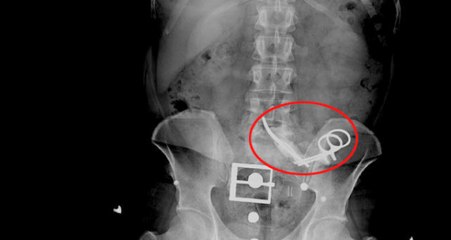

Kayseri'de 16 yıl önce tüfekle vurulan Kadir Durdu'nun sol bacağında ameliyat sırasında unutulan bez parçası bulundu. Durdu, yaşadığı mağduriyetin giderilmesi ve sorumluların cezalandırılmasını istiyor. brKAYSERİ'de 16 yıl önce tüfekle vurulan Kadir Durdu'nun (41) yaralanan sol bacağında, o dönem yapılan ameliyatta bez parçası unutulduğu ortaya çıktı. Kadir Durdu, 15-16 senedir bir kumaş parçasıyla yaşamışım. Bunu yapanların ceza almasını istiyorum dedi.brKayseri'de 16 yıl önce husumetli olduğu kişilerle tartışan Kadir Durdu, tüfekle sol bacağından yaralandı. Erciyes Üniversitesi Tıp Fakültesi Hastanesi'ne götürülen Durdu, bir hafta yoğun bakımda kaldı. Tedavisi tamamlanan Kadir Durdu, asker firarisi olduğu için Diyarbakır E Tipi Cezaevi'ne götürüldü. Bu süreçte ağrıların şiddetlenmesiyle Dicle Üniversitesi Hastanesi'ne kontrole giden Kadir Durdu, sol bacağından ameliyat oldu.br br hbrlr1.